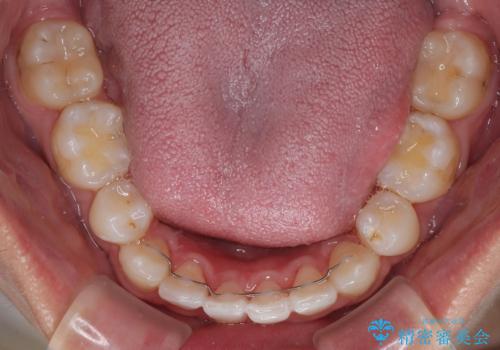

治療後には、デコボコと正中の位置が改善し、見た目だけでなく歯磨きがしやすい清潔なお口の環境を手に入れました。